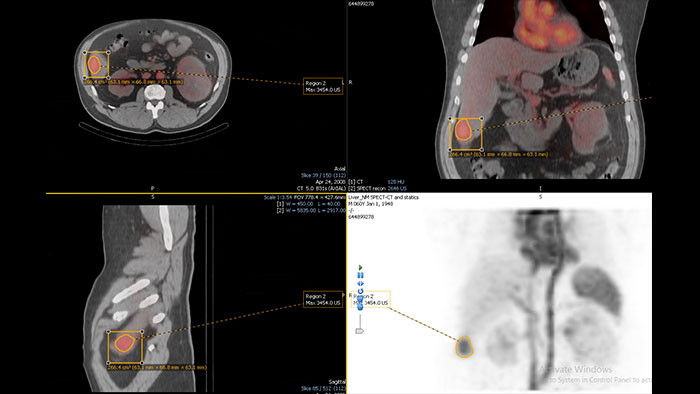

Streamlined workflow for follow up and analysis of oncology patients

MMTT is a post processing software used to display, process, analyze and quantify anatomical and functional images, for CT, MR, PET/CT, SPECT/CT and Dual Energy CT at one or multiple time points.